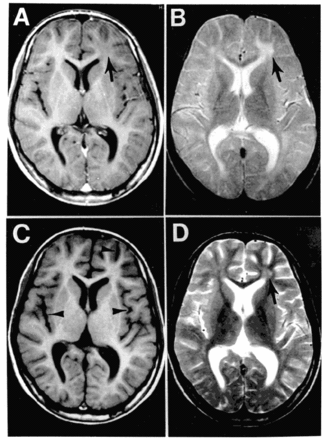

Op een EEG kan de karakteristieke periodische activiteit waargenomen worden, het rademeckercomplex, die wijd verspreide corticale disfunctie laat zien. De witte stof van beide hemisferen en de hersenstam is aangetast, net als de cortex cerebri. De diagnose is vaak moeilijk te stellen doordat het hersenvocht er normaal uitziet, met enkel maar een verhoogd immunoglobulineniveau.